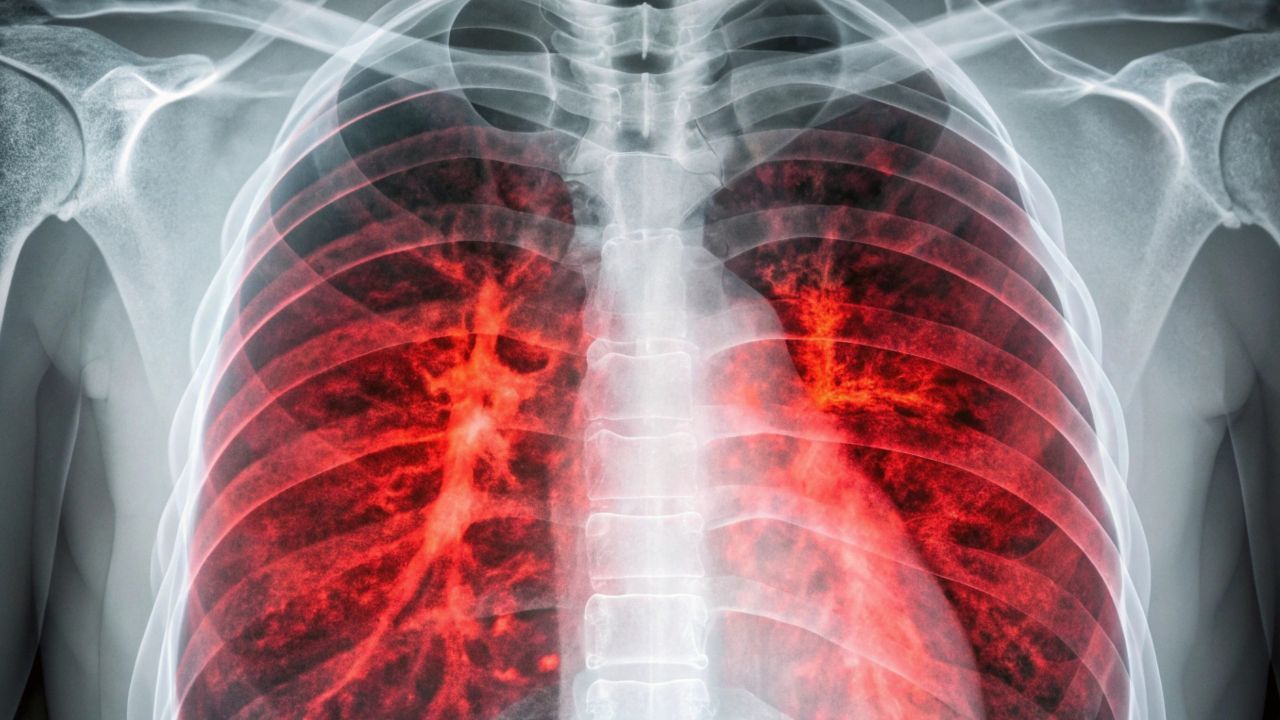

To znak, że rak zajął płuca. Może dotyczyć nawet 70 proc. chorych

Gdy kaszel trwa tygodniami i nie reaguje na syrop ani antybiotyk, wielu zrzuca winę na „ciągnące się przeziębienie”. Tymczasem uporczywy kaszel to najczęstszy sygnał, że w płucach rozwinął się nowotwór lub pojawiły się jego przerzuty. Dlaczego właśnie ten objaw dotyczy aż 70 proc. pacjentów i co mówią najnowsze statystyki?